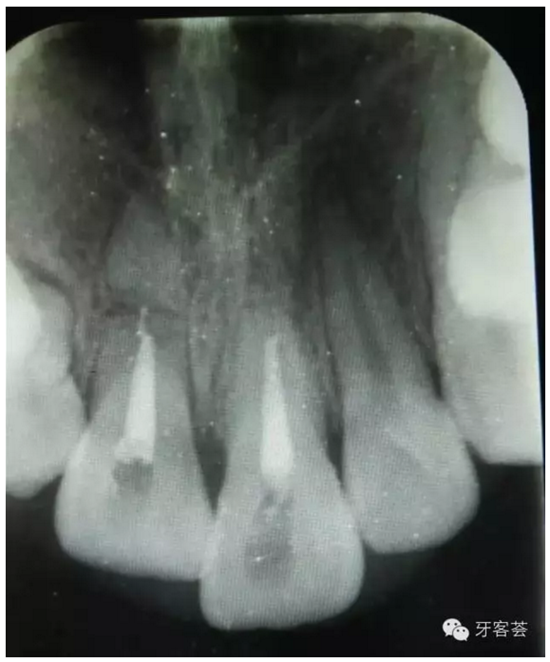

圖3:根尖片可以清晰看到11、21根尖橫折,這是根管治療過(guò)程中的試尖。

圖4:根充完成后,11根尖橫折。21根尖橫折部分已經(jīng)骨化。擬行11根尖斷根取出術(shù)及12拔除。